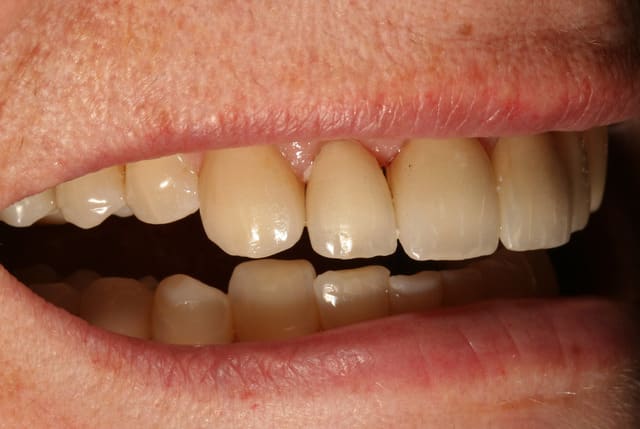

essayage, et comme on peut le voir sur la première photo, c'est bizarement long par rapport au provisoire ...

pourtant le prothésiste avait un alginate des mocks-up

j'ai mis du sealtemp et essayé tout ça, c'est trop long

par contre, je me dis que je suis resté trop supra-gingival sur mes préparations, ça se voit trop, même si la patiente découvre peu, elle découvre un peu et j'aurais du aller plus juxta.